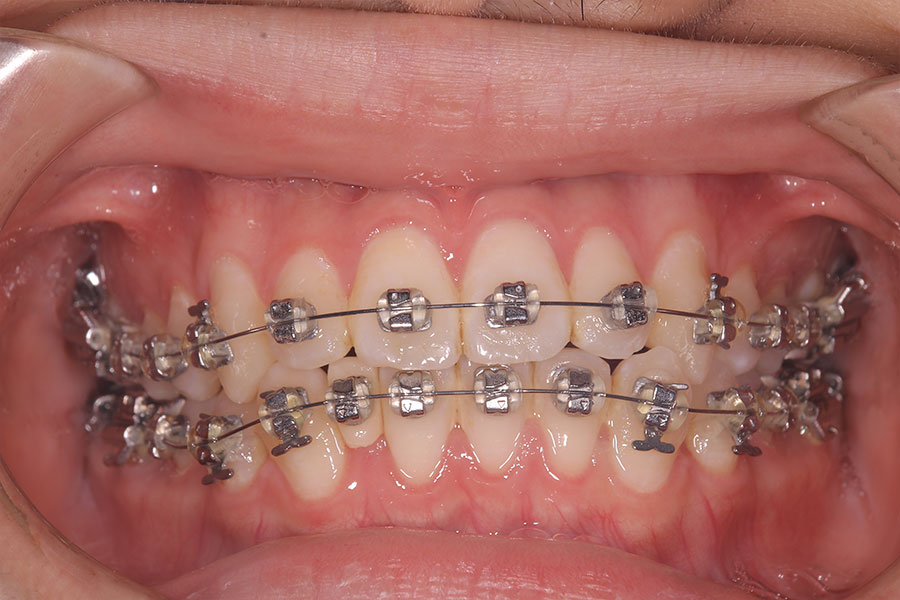

Before -正面-

After -正面-

Before -側面-

After -側面-

| 施術内容 | ワイヤー矯正から、目立ちにくくメタルフリーなインビザラインへ変更しました。 金属アレルギーの不安が軽くなり、取り外しできることで清掃性も向上。見た目も自然で、治療中のストレスが少ない矯正方法です。 |

|---|---|

| 治療期間 | 2年間 |

| 費用 | インビザラインフル 767,800円 リテーナー 30,000円 |

| リスク・副作用 | 治療にともない、歯の破折や歯質の削合、場合によっては抜歯が必要となることがあります。また、金属や補綴物を除去する際に、完全に除去できない場合もあります。 |